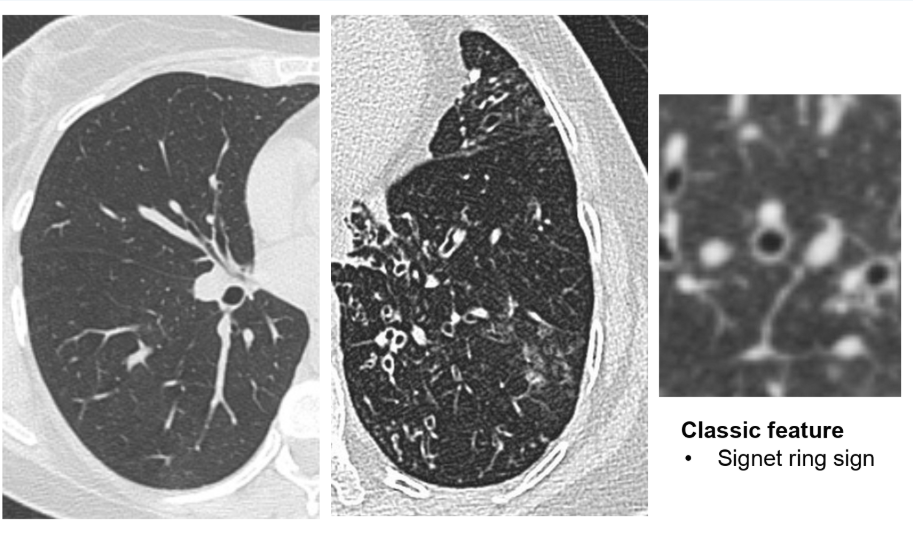

GOLD STANDARD- High resolution CT

=dilated terminal airways

= signet sign